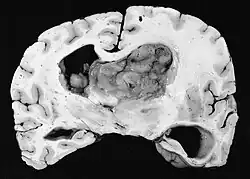

| GFAP stained microscopic section of a subependymal giant cell astrocytoma | |